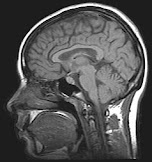

Imagen1 del cerebro con resonancia magnética, obtenida de :

https://upload.wikimedia.org/wikipedia/commons/3/3b/MRI_brain.jpg